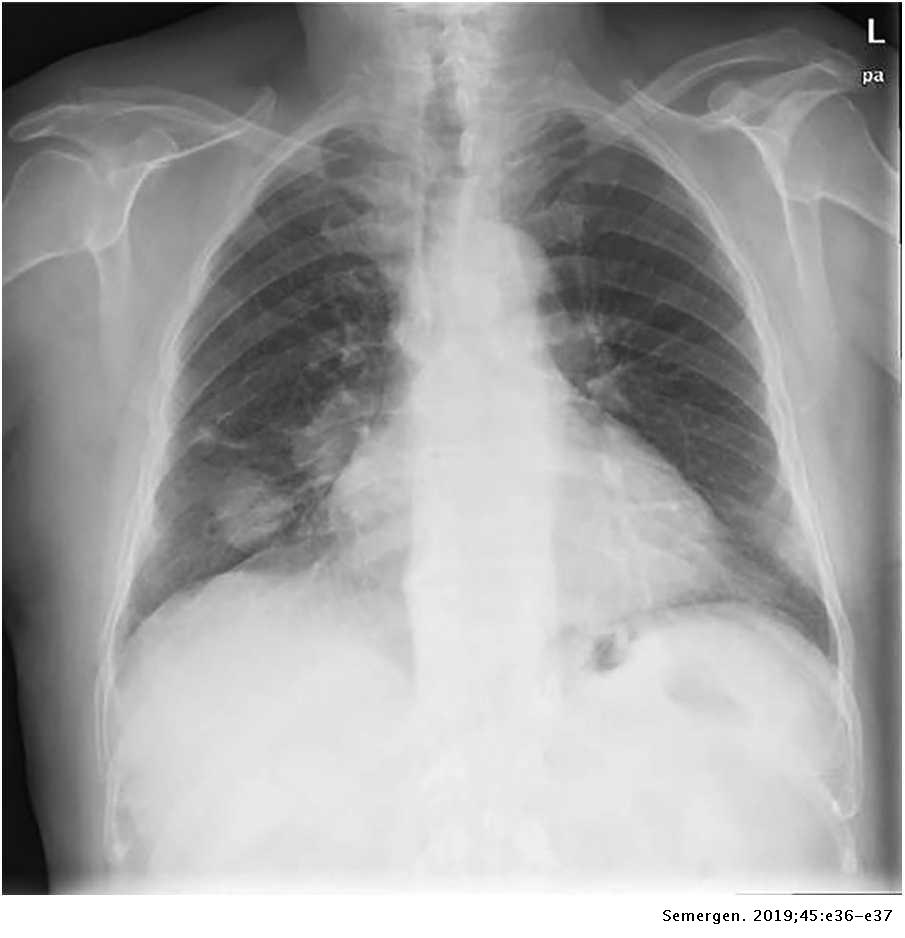

Lista es una colección y muestra de imágenes sobre imagenes de pulmones sanos y enfermos realizada por upup.edu.vn. Además, hay imágenes relacionadas con imagenes de pulmones sanos, imágenes de pulmones sanos, radiografía de pulmones sanos y enfermos, fotos de pulmones sanos, radiografía pulmones sanos y enfermos, rayos x de pulmones sanos y enfermos, pulmon sano y enfermo, pulmón sano y enfermo . Para más información, consulta a continuación.

imagenes de pulmones sanos y enfermos

Posts: imagenes de pulmones sanos y enfermos